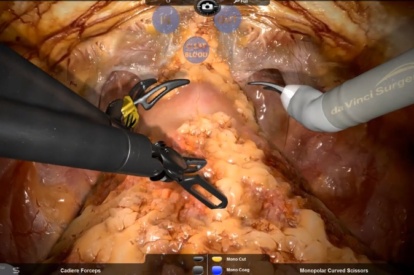

- Highly realistic graphics of human anatomy and simulation of tissue response to instruments

- Complication management: simulation of errors and bleedings

- Tutorials: videos of experts performing tasks and procedures on the simulator along with videos of real procedures